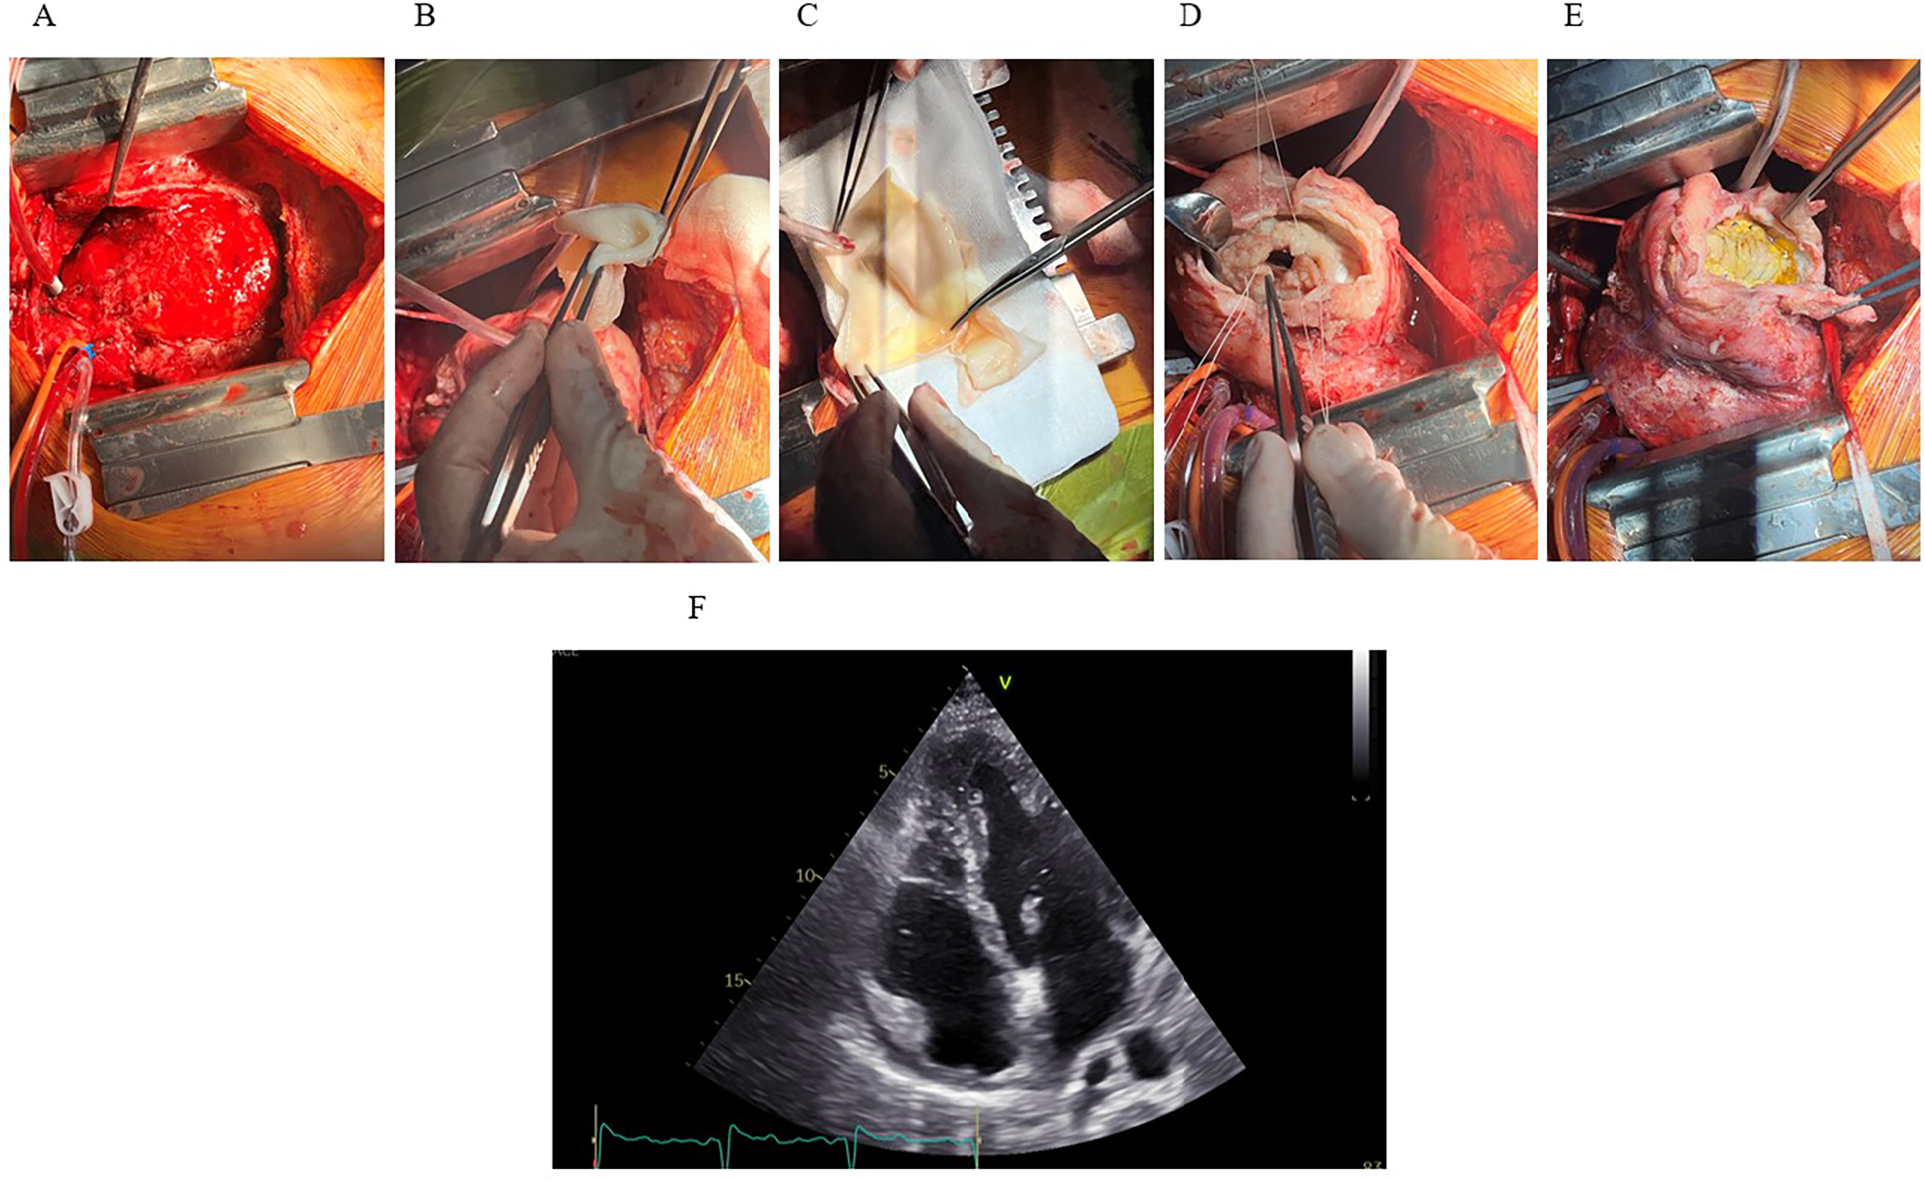

On day 31, the patient was transferred to the operating room, where first the median sternotomy and thorough adhesioloysis of the heart were performed. After sufficient exposure of the left ventricle, the LV aneurysm was opened and an endoventricular circular patch repair (i.e., Dor procedure) of the left ventricle performed using intraoperative tailored bovine pericardial patch (Abbot®, USA) shaped in an elliptical form measuring approximately 5 × 3 centimeters. Due to known ischemic aetiology of the disease no samples of the aneurysmatic tissue was sent for pathology, however, samples of the intramural hematoma were sent for microbiology to exclude the infective component of the disease (Figure 4). The chest was left open for delayed sternal closure and was subsequently closed on the next day once patient's complete hemodynamic stability and adequate haemostasis were established. No additional temporary mechanical circulatory support to achieve patient's hemodynamic stability was needed throughout the perioperative period.

Figure 4

The Dor procedure and outcome. (A) Median sternotomy reveals the heart exposed, showing extensive hematoma and inflammation involving the inferoapical myocardial region. (B,C) A synthetic patch for reconstruction of the LV geometry. (D) LV cavity exposed following resection of infarcted and necrotic myocardium. Sutures placed around the cavity for patch attachment. (E) Final positioning and fixation of the synthetic patch. (F) Postoperative TTE (apical four-chamber view) demonstrates successful resolution of the IDH and intracavitary thrombus, with only residual apical hypokinesis.

The patient tolerated the procedures well and was extubated on day two, post-operative course was insignificant. A TTE, performed 9 days after surgery revealed good LV systolic function with left-ventricular ejection fraction (LVEF) of 54% and slightly reduced left-ventricular outflow tract (LVOT) velocity-time integral (VTI) of 13 cm (stroke volume 22 mL/m2) with hypokinesia of apical septal segment and akinesia of apical inferior segment (Figure 4). Antibiotic treatment was completed on day 8 after surgery with no clinical signs of infection and low inflammatory markers.